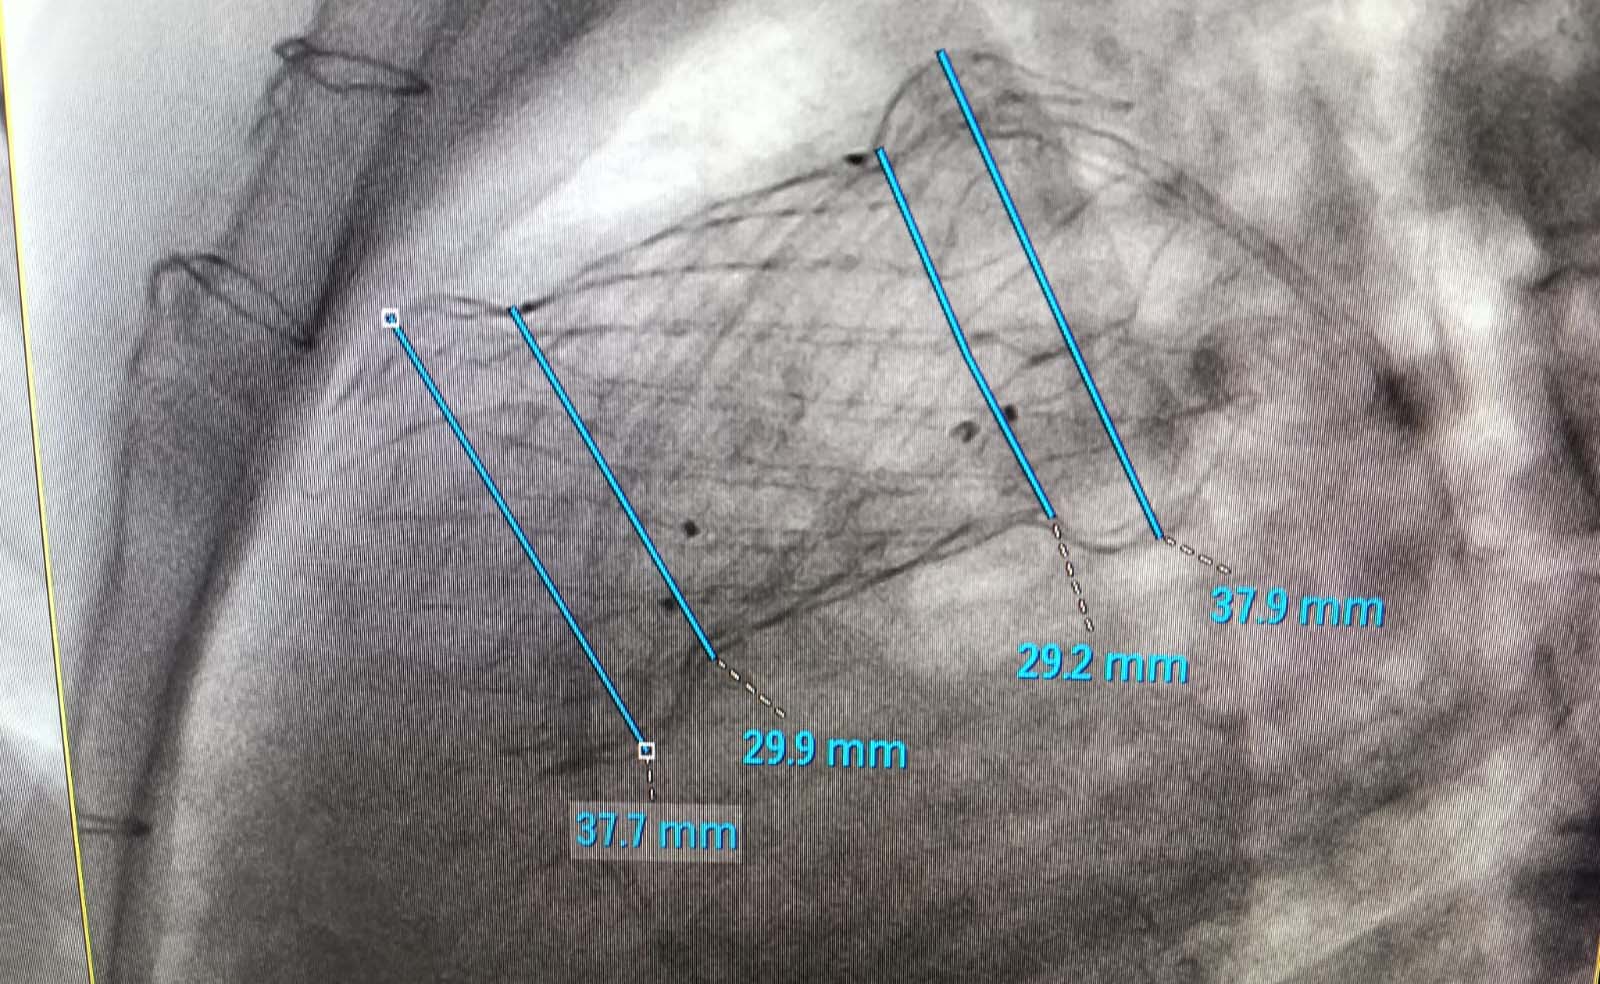

The Paediatric Cardiology team at Peshawar Institute of Cardiology (PIC-MTI), under the leadership of Prof. Ijaz Hussain, successfully performed transcatheter pulmonary valve implantation procedures in three patients. The procedures were conducted with the valuable support and supervision of a visiting team of paediatric cardiologists from Thailand,reflecting PIC’s commitment to international collaboration and clinical excellence. All patients recovered well following the procedures and have been safely discharged. PIC-MTI continues to provide advanced, high-end tertiary cardiac care services to the people of Pakistan. These achievements are made possible through the continued support of the Government of Khyber Pakhtunkhwa, ensuring timely funding and strengthening specialized healthcare services in the province.